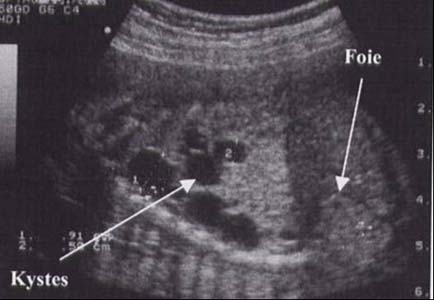

MAKP - macrokystique